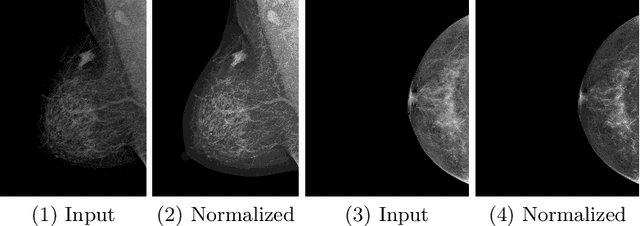

Abstract:Grading breast density is highly sensitive to normalization settings of digital mammogram as the density is tightly correlated with the distribution of pixel intensity. Also, the grade varies with readers due to uncertain grading criteria. These issues are inherent in the density assessment of digital mammography. They are problematic when designing a computer-aided prediction model for breast density and become worse if the data comes from multiple sites. In this paper, we proposed two novel deep learning techniques for breast density prediction: 1) photometric transformation which adaptively normalizes the input mammograms, and 2) label distillation which adjusts the label by using its output prediction. The photometric transformer network predicts optimal parameters for photometric transformation on the fly, learned jointly with the main prediction network. The label distillation, a type of pseudo-label techniques, is intended to mitigate the grading variation. We experimentally showed that the proposed methods are beneficial in terms of breast density prediction, resulting in significant performance improvement compared to various previous approaches.